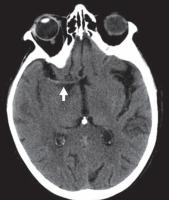

图 3A —患有线粒体脑肌病、乳酸性酸中毒和中风样发作 (MELAS) 的梗死患者的 MR 图像。T2 加权图像显示两个枕叶信号增加,右侧(粗箭头)大于左侧(细箭头)。

图 3B —患有线粒体脑肌病、乳酸性酸中毒和中风样发作 (MELAS) 的梗死患者的 MR 图像。弥散加权图像也显示双侧高信号,右侧(粗箭头)大于左侧(细箭头)。

图 3C —患有线粒体脑肌病、乳酸性酸中毒和中风样发作 (MELAS) 的梗死患者的 MR 图像。表观扩散系数图像(ADC)显示右侧信号减弱(粗箭头)但左侧信号正常(细箭头)。因此,右侧病变为急性梗死,弥散受限。左侧病变代表亚急性或慢性梗塞,弥散加权图像上有 T2 透过效应。

MRI 也可用于急性卒中,尽管技术和人员要求限制了它在许多中心的应用。DWI 是检测超急性梗塞(出现后 < 30 分钟)最敏感的序列,先于 CT(6 小时)和 T2 加权成像(6-12 小时)识别病情变化。急性梗塞中的扩散受限分别对应于 DWI 和 ADC 图上信号增加和减少的区域。随着梗死发展为亚急性和慢性阶段,会发展为血管源性水肿和脑软化症。这反映在 T2/FLAIR 信号强度的逐渐增加,且伴随着扩散系数的正常化(图3A ), 3B, 和3C)。也可以进行3D-TOF MRA或者3D-ASL检查。然而,与 CT 相比,空间分辨率较差,图像容易出现运动、磁化率和流动伪影。